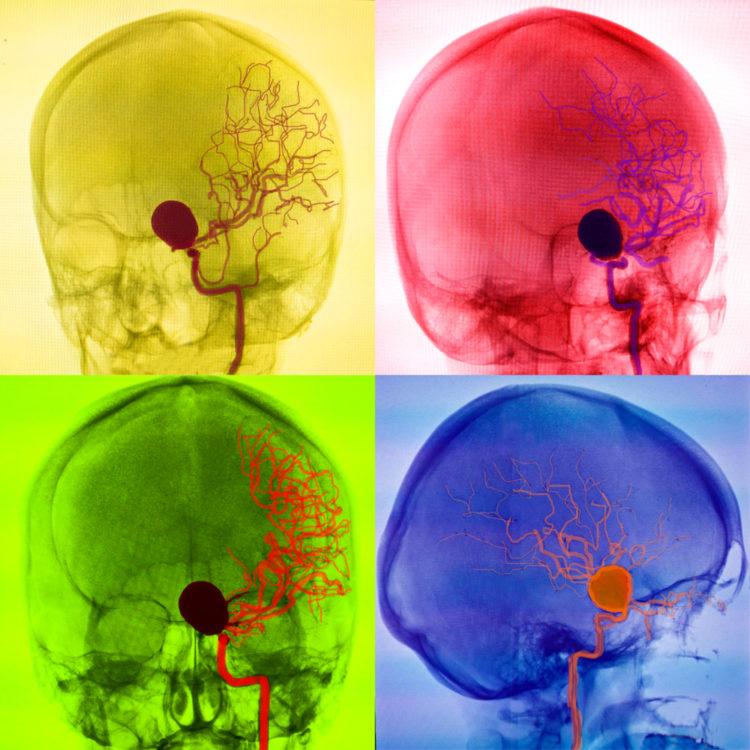

Chụp mạch máu não là một xét nghiệm được dùng để quan sát xem các mạch máu cung cấp máu ở đầu và cổ cung cấp máu cho não có bị hẹp hay tắc nghẽn không. Những bất thường hẹp hay tắc nghẽn này có thể gây ra bệnh đột quỵ hoặc bệnh phình động mạch.

Trong quá trình làm xét nghiệm, bác sĩ thường dùng một ống thông dài và dẻo để luồn nó tới các mạch máu ở đầu và cổ. Sau đó, thuốc cản quang sẽ được bơm vào mạch máu qua ống thông này. Nhờ có thuốc cản quang, hình ảnh của các động mạch sẽ được làm nổi rõ lên và hiển thị rất chi tiết trong phim chụp x-quang. Từ đó, bác sĩ có thể xác định được động mạch nào bị hẹp.

Chụp mạch máu não (chụp mạch máu não) được sử dụng để đánh giá tình trạng các tĩnh mạch hoặc bốn động mạch lớn có chức năng đưa máu lên não.